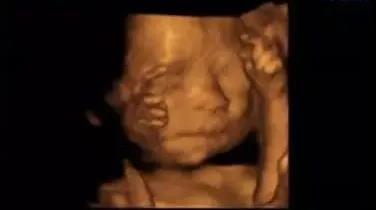

福利二:四維/5D彩超曬照集贊有禮

曬照需配上文字“雅安恒博醫(yī)院四維/5D彩超+自己想說的話”,集贊滿88個(gè),即可獲得:

雅安恒博醫(yī)院送出的兒童音樂搖搖木馬一個(gè)+雅安奶滋坊提供的30元無門檻代金券一張。